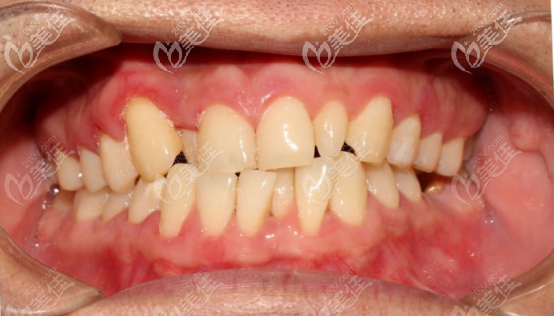

術(shù)前正面照

術(shù)前自我認為的牙齒問題:

牙列擁擠,不整齊,缺牙,牙齒歪斜,有兩個過于小的牙齒,影響咀嚼。